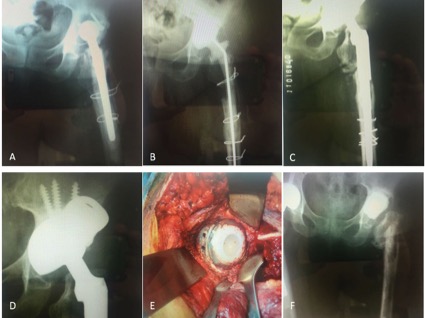

Introducción: El objetivo de este estudio es analizar nuestros resultados clínico-radiológicos con el uso de copas de tantalio trabecular para la reconstrucción de acetábulos complejos, tanto en cirugías primarias como en revisiones, y com- pararlos con series similares de otros autores. Materiales y Métodos: Se llevó a cabo una revisión retrospectiva de una serie de 42 cirugías (29 revisiones y 13 artro- plastias primarias) en 40 pacientes, entre marzo de 2010 y marzo de 2016. La serie incluyó a 20 mujeres y 20 hombres, con una edad promedio de 60 años (rango 27-93). El seguimiento promedio fue de 37 meses (rango 12-84). Todos los pacientes fueron tratados con el mismo tipo de metal trabecular. Resultados: Al promedio de seguimiento mencionado la supervivencia del componente acetabular fue del 97,6%. Un paciente fue tratado con artroplastia de resección debido a una infección persistente. La tasa de complicaciones totales fue del 12% y el promedio del Harris Hip Score posoperatorio fue de 81,54 (rango 63,25-92,75). Conclusiones: Aunque se necesita un seguimiento más prolongado, el uso de copas de metal trabecular logra resultados prometedores para el tratamiento de acetábulos complejos.